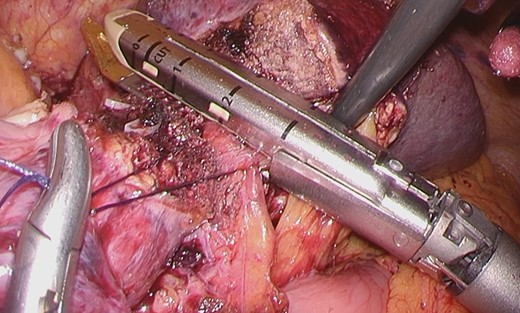

Considering the small remnant right lobe and abnormal ICG15, we planned to perform laparoscopic anatomical S3 segmentectomy. The procedures were performed using a pressure-controlled carbon dioxide pneumoperitoneum, which was maintained below 12 mmHg. Intraoperative findings showed hypoplasia of the right hepatic lobe and hypertrophy of the left hepatic lobe (Fig. 2). Intraoperative ultrasound (IOUS) was performed to confirm the location of the tumor and its relationship to the adjacent structures. The Glissonian pedicle to S3 was isolated with meticulous dissection and was then transected using the SigniaTM Stapling System and Endo GIATM Curved Tip Reload with Tri-StapleTM Technology 30 mm, Vascular Medium (Covidien, USA) (Fig. 3). The ischemic margin of S3 was marked using electrocautery (Fig. 4). Using the crush-clamp method with a harmonic scalpel (Ethicon, USA), the liver parenchyma was transected along the left hepatic vein (Fig. 5). Pringle’s maneuver was performed by clamping the hepatoduodenal ligament using the tourniquet method for 15 min with following a 5-min release period, and a total of fourteen temporary clamps were performed during parenchymal resection. The resected specimens were removed in a retrieval bag through an umbilical port site. The resected specimen showed a 41-mm simple nodular type of HCC and a 5-mm tumor-free resection margin (Fig. 6). Each port was placed as shown in Fig. 7.

The liver parenchyma was transected along the left hepatic vein.